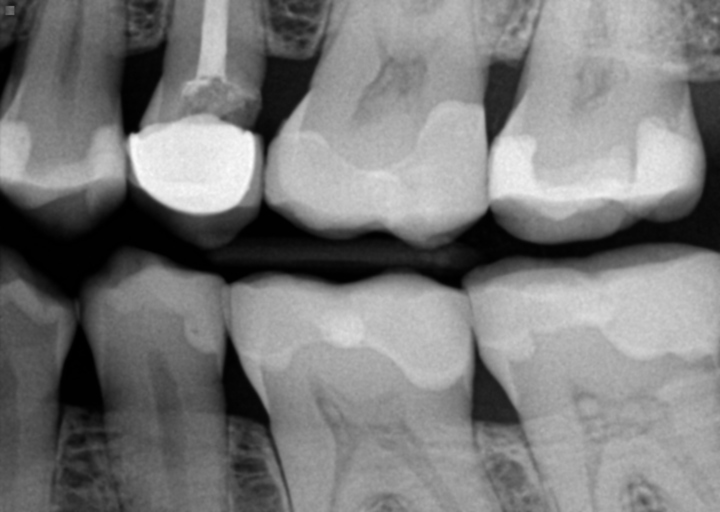

Hello, I just got temporary crowns on one side of my top arch and will get temporary crowns on the other side. Early February Ill get the permanent crowns. However, I have been wearing my retainers every night for two years as instructed, but am worried they will shift from today to early February. Can I have advice? Im bringing my retainers tomorrow so my dentist can adjust them but keep in mind the other side will need temporary crowns too. Notice how on the photo that the retainer hangs under the temporary crowns, as they are very thick.